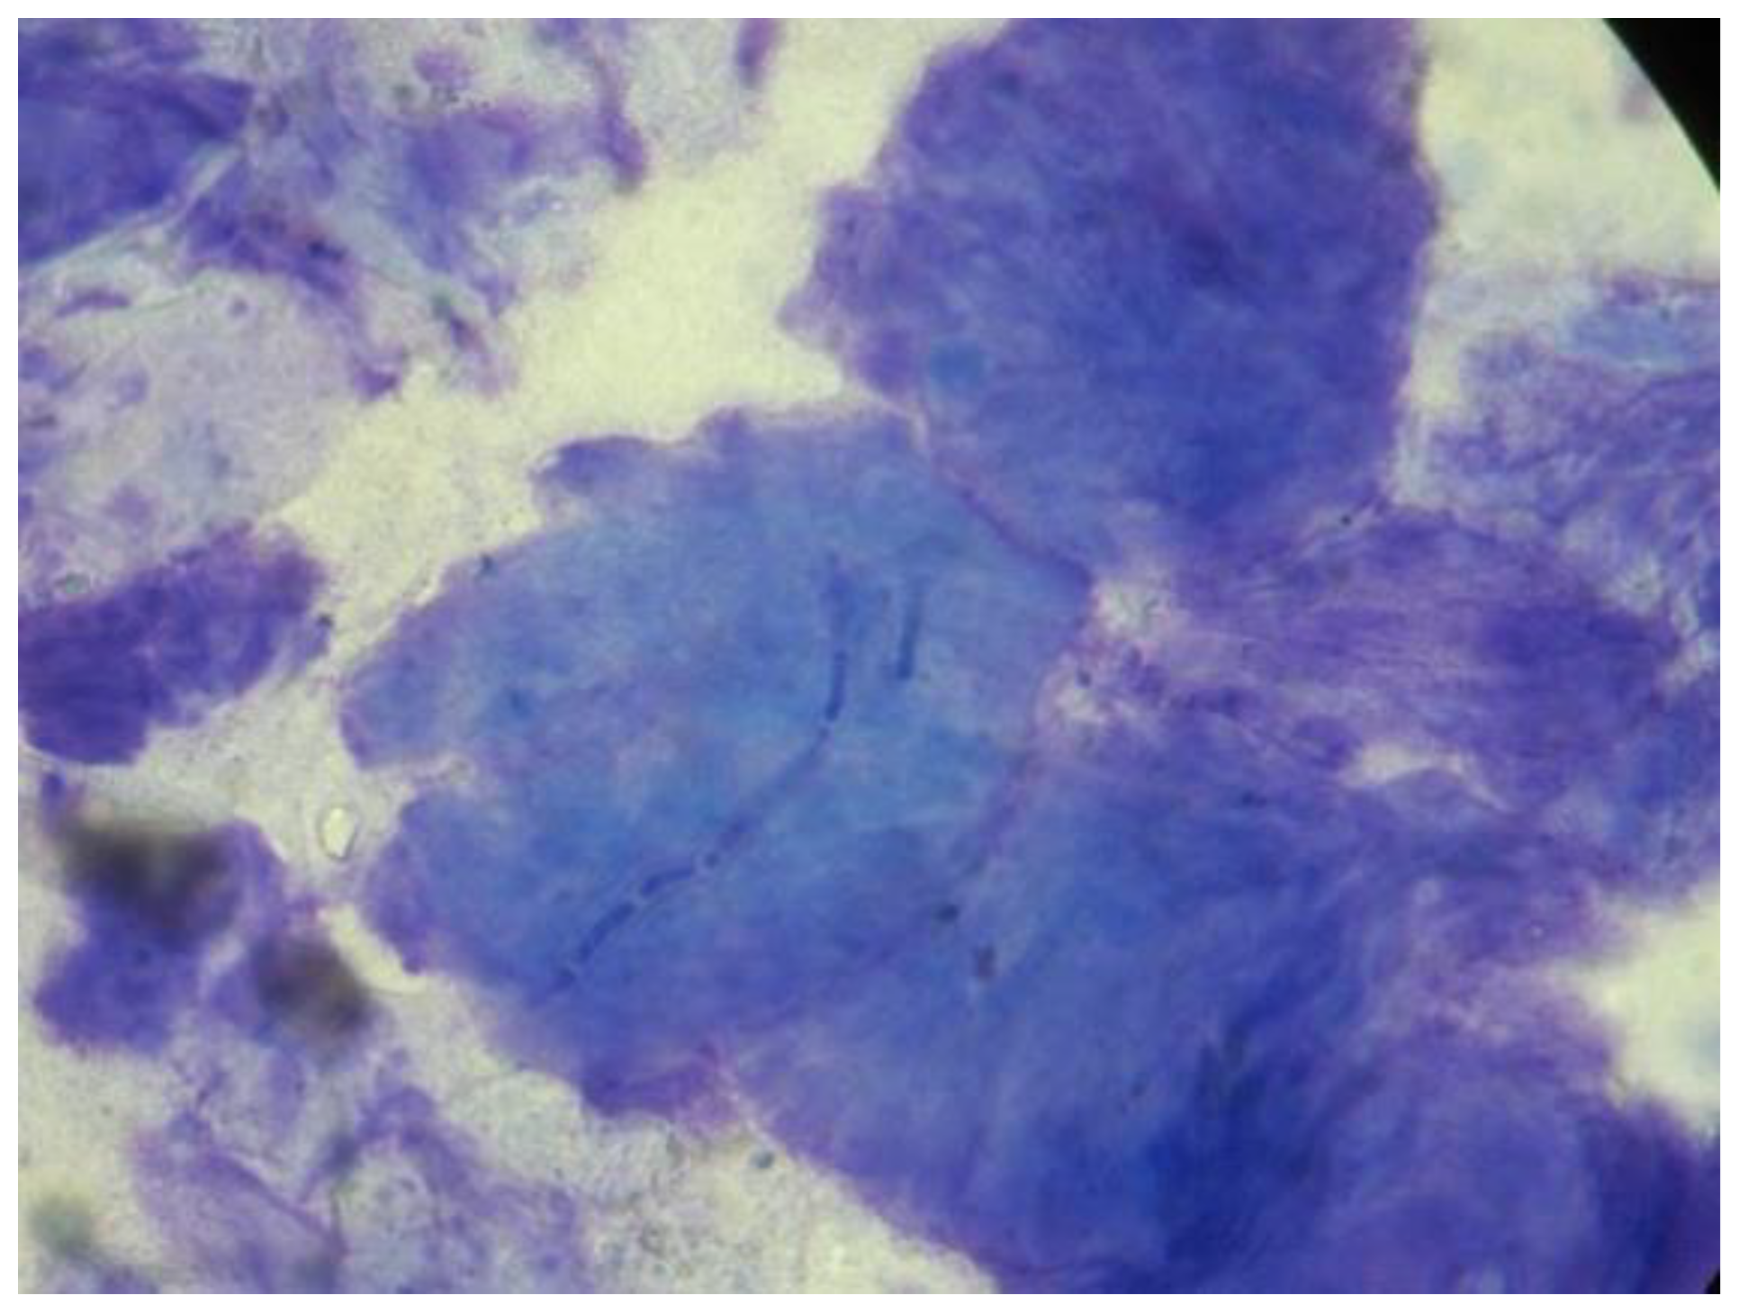

The results of the diagnostic tests of the 30 dogs are presented in Table 2. In nine dogs all three tests (9/30, 30%) were positive, in sixteen dogs two of the tests (16/30, 53.3%) were positive, and in five dogs only one (5/30, 16.7%) test was positive. The sensitivity of each diagnostic test with the corresponding 95% confidence interval (C.I.) within different animals’ groups is presented in Table 3 Hyphae and spores were seen in 78.3% (18/23) and 65.2% (15/23) of the positive adhesive tape preparations, respectively (Figure 1). M. canis was isolated in 95.7% (22/23) of the positive fungal cultures, while M. canis and T. mentagrophytes were isolated in one case (1/23, 4.3%).

Figure 1.

Adhesive tape impression cytology from a dog with dermatophytosis showing a hypha on the surface of a corneocyte (100×).